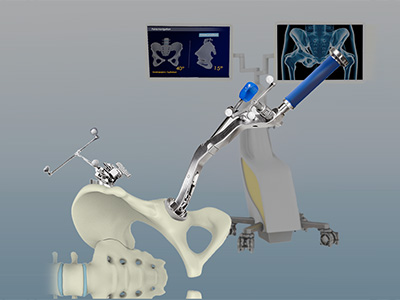

Anterior Hip Replacement Robotic Assisted Hip Replacement

Robotic Total Hip Replacement ROSA Robotic-Assisted Anterior Hip Replacement

ROSA Robotic-Assisted Anterior Hip Replacement Muscle Sparing Anterior Hip Replacement

Muscle Sparing Anterior Hip Replacement Anterior Hip Replacement with Navigation

Anterior Hip Replacement with Navigation Rapid Recovery Hip Replacement

Complex Primary Hip Replacement Computer-assisted Hip Replacement

Computer-assisted Hip Replacement Computer-Navigated Total Hip Replacement

Computer-Navigated Total Hip Replacement Revision Hip Surgery